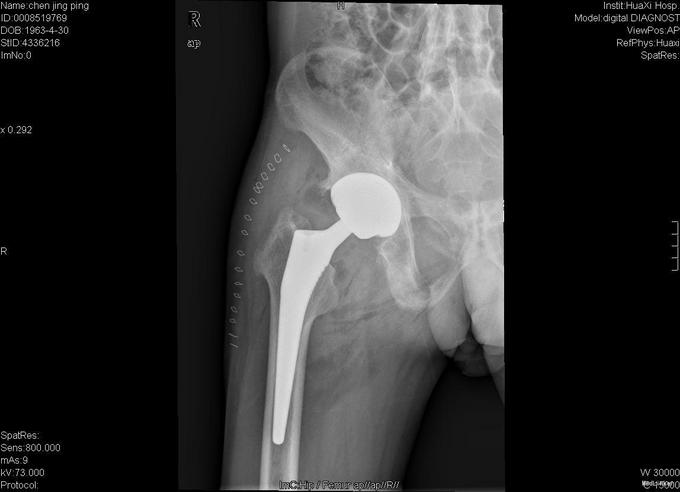

查体:跛行步态,强迫体位,脊柱强直后凸畸形,活动受限。右髋强直畸形,压痛、叩痛,无瘢痕、窦道,无皮损、皮癣,活动受限。双下肢感觉无明显异常。 辅助检查:x线片:脊柱呈"竹节样"改变,腰椎小关节间隙模糊,双侧骶髂关节及右髋关节间隙消失,骨性融合。

诊断:强直性脊柱炎 右髋关节强直 治疗:完善相关检查后在全麻下行右侧全髋关节置换术+髋臼成形术,手术顺利,术后予以抗炎+抗凝+阵痛等治疗。

术后患者恢复良好,右髋屈曲100°,伸直0°,外展40° 1、强直性脊柱炎起病特点有哪些 2、实验室检查及影像学表现有何特点? 3、治疗原则及主要治疗方法有哪些?